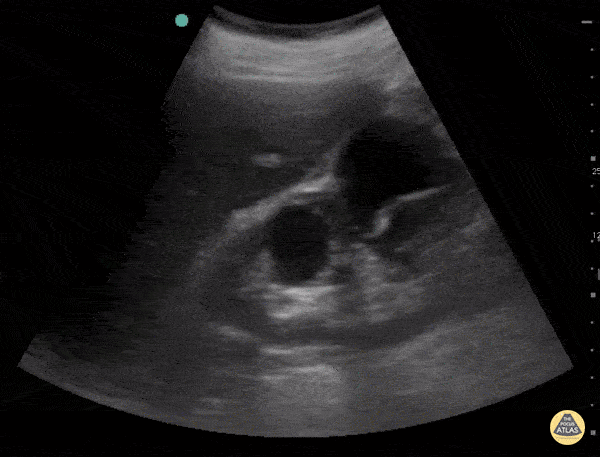

Renal cysts can be classified using the Bosniak Classification System based on CT imaging. A category I benign cyst is thin-walled without septations, calcifications, solidifications, nor contrast enhancement. A category II benign cyst is also thin-walled but may contain a few thin septa or calcifications. A category IIF cyst has a small risk of malignancy. It may have a slightly thicker wall, septa or calcifications, but no contrast enhancement. A category III cyst has a significant risk of malignancy and has irregular and thick septa which exhibit contrast enhancement. A category IV cyst (highest risk) has category 3 characteristics with the addition of contrast enhancing soft tissue components. This clip shows septation of one of the cysts suggesting that it is AT LEAST a category 2 cyst. Sukh Singh, MD